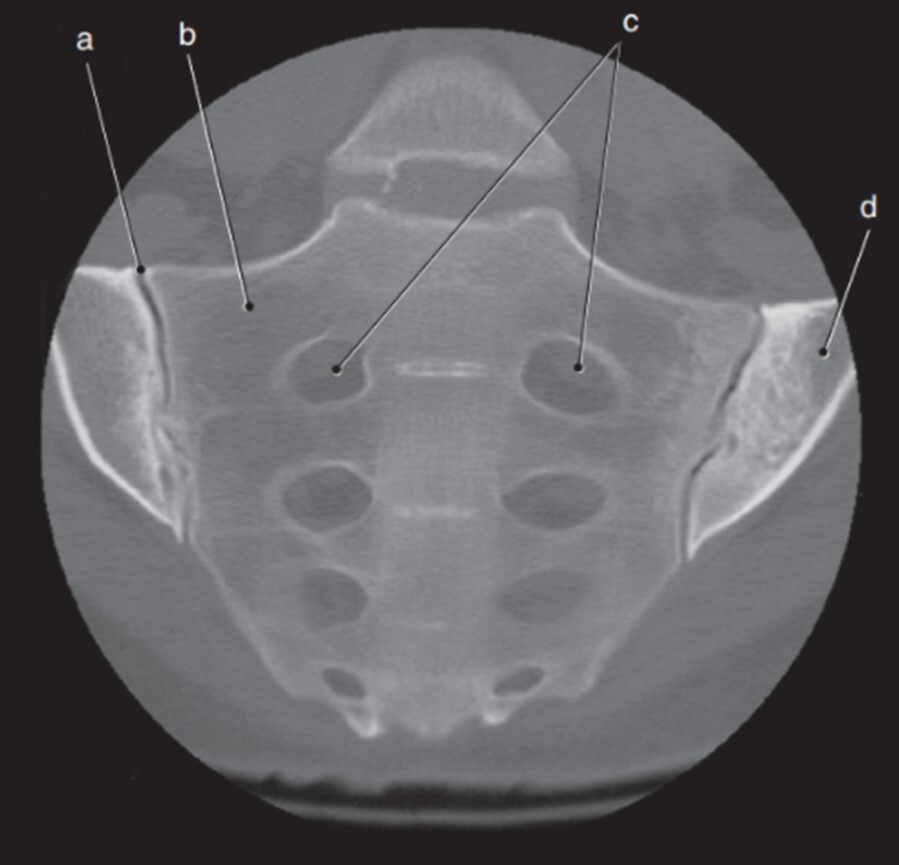

Q

Label a-d

A

a. Rt SI joint

b. Rt lateral mass (sacrum)

c. Sacral foramina

d. Lt ilium